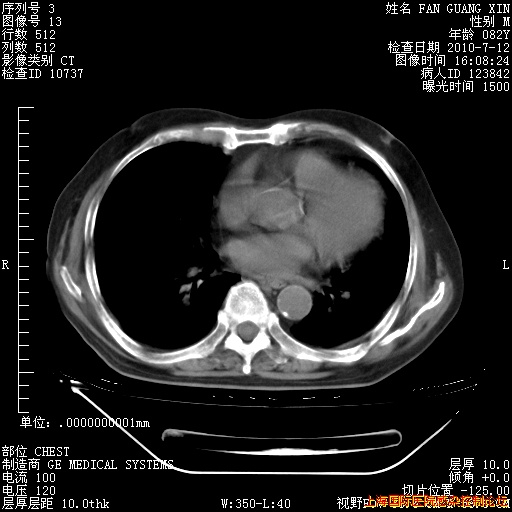

6月12日肺窗

6月12日纵膈窗

今天复查CT

今天CT

整整相隔30天的肺部CT好像有所好转啊。甲强龙减量第3天,需要观察体温。

海管,自昨日你和我通完话后,不知您岳父消化道症状有无缓解?体温怎样?阅读7.12日胸部ct,个人认为目前激素治疗是有效的,甲强龙减量是适宜的。因在抗痨治疗,需密切观察肝功、肾功能和血常规。不过,老年、长期住院和大量使用激素,很担心菌群失调发生